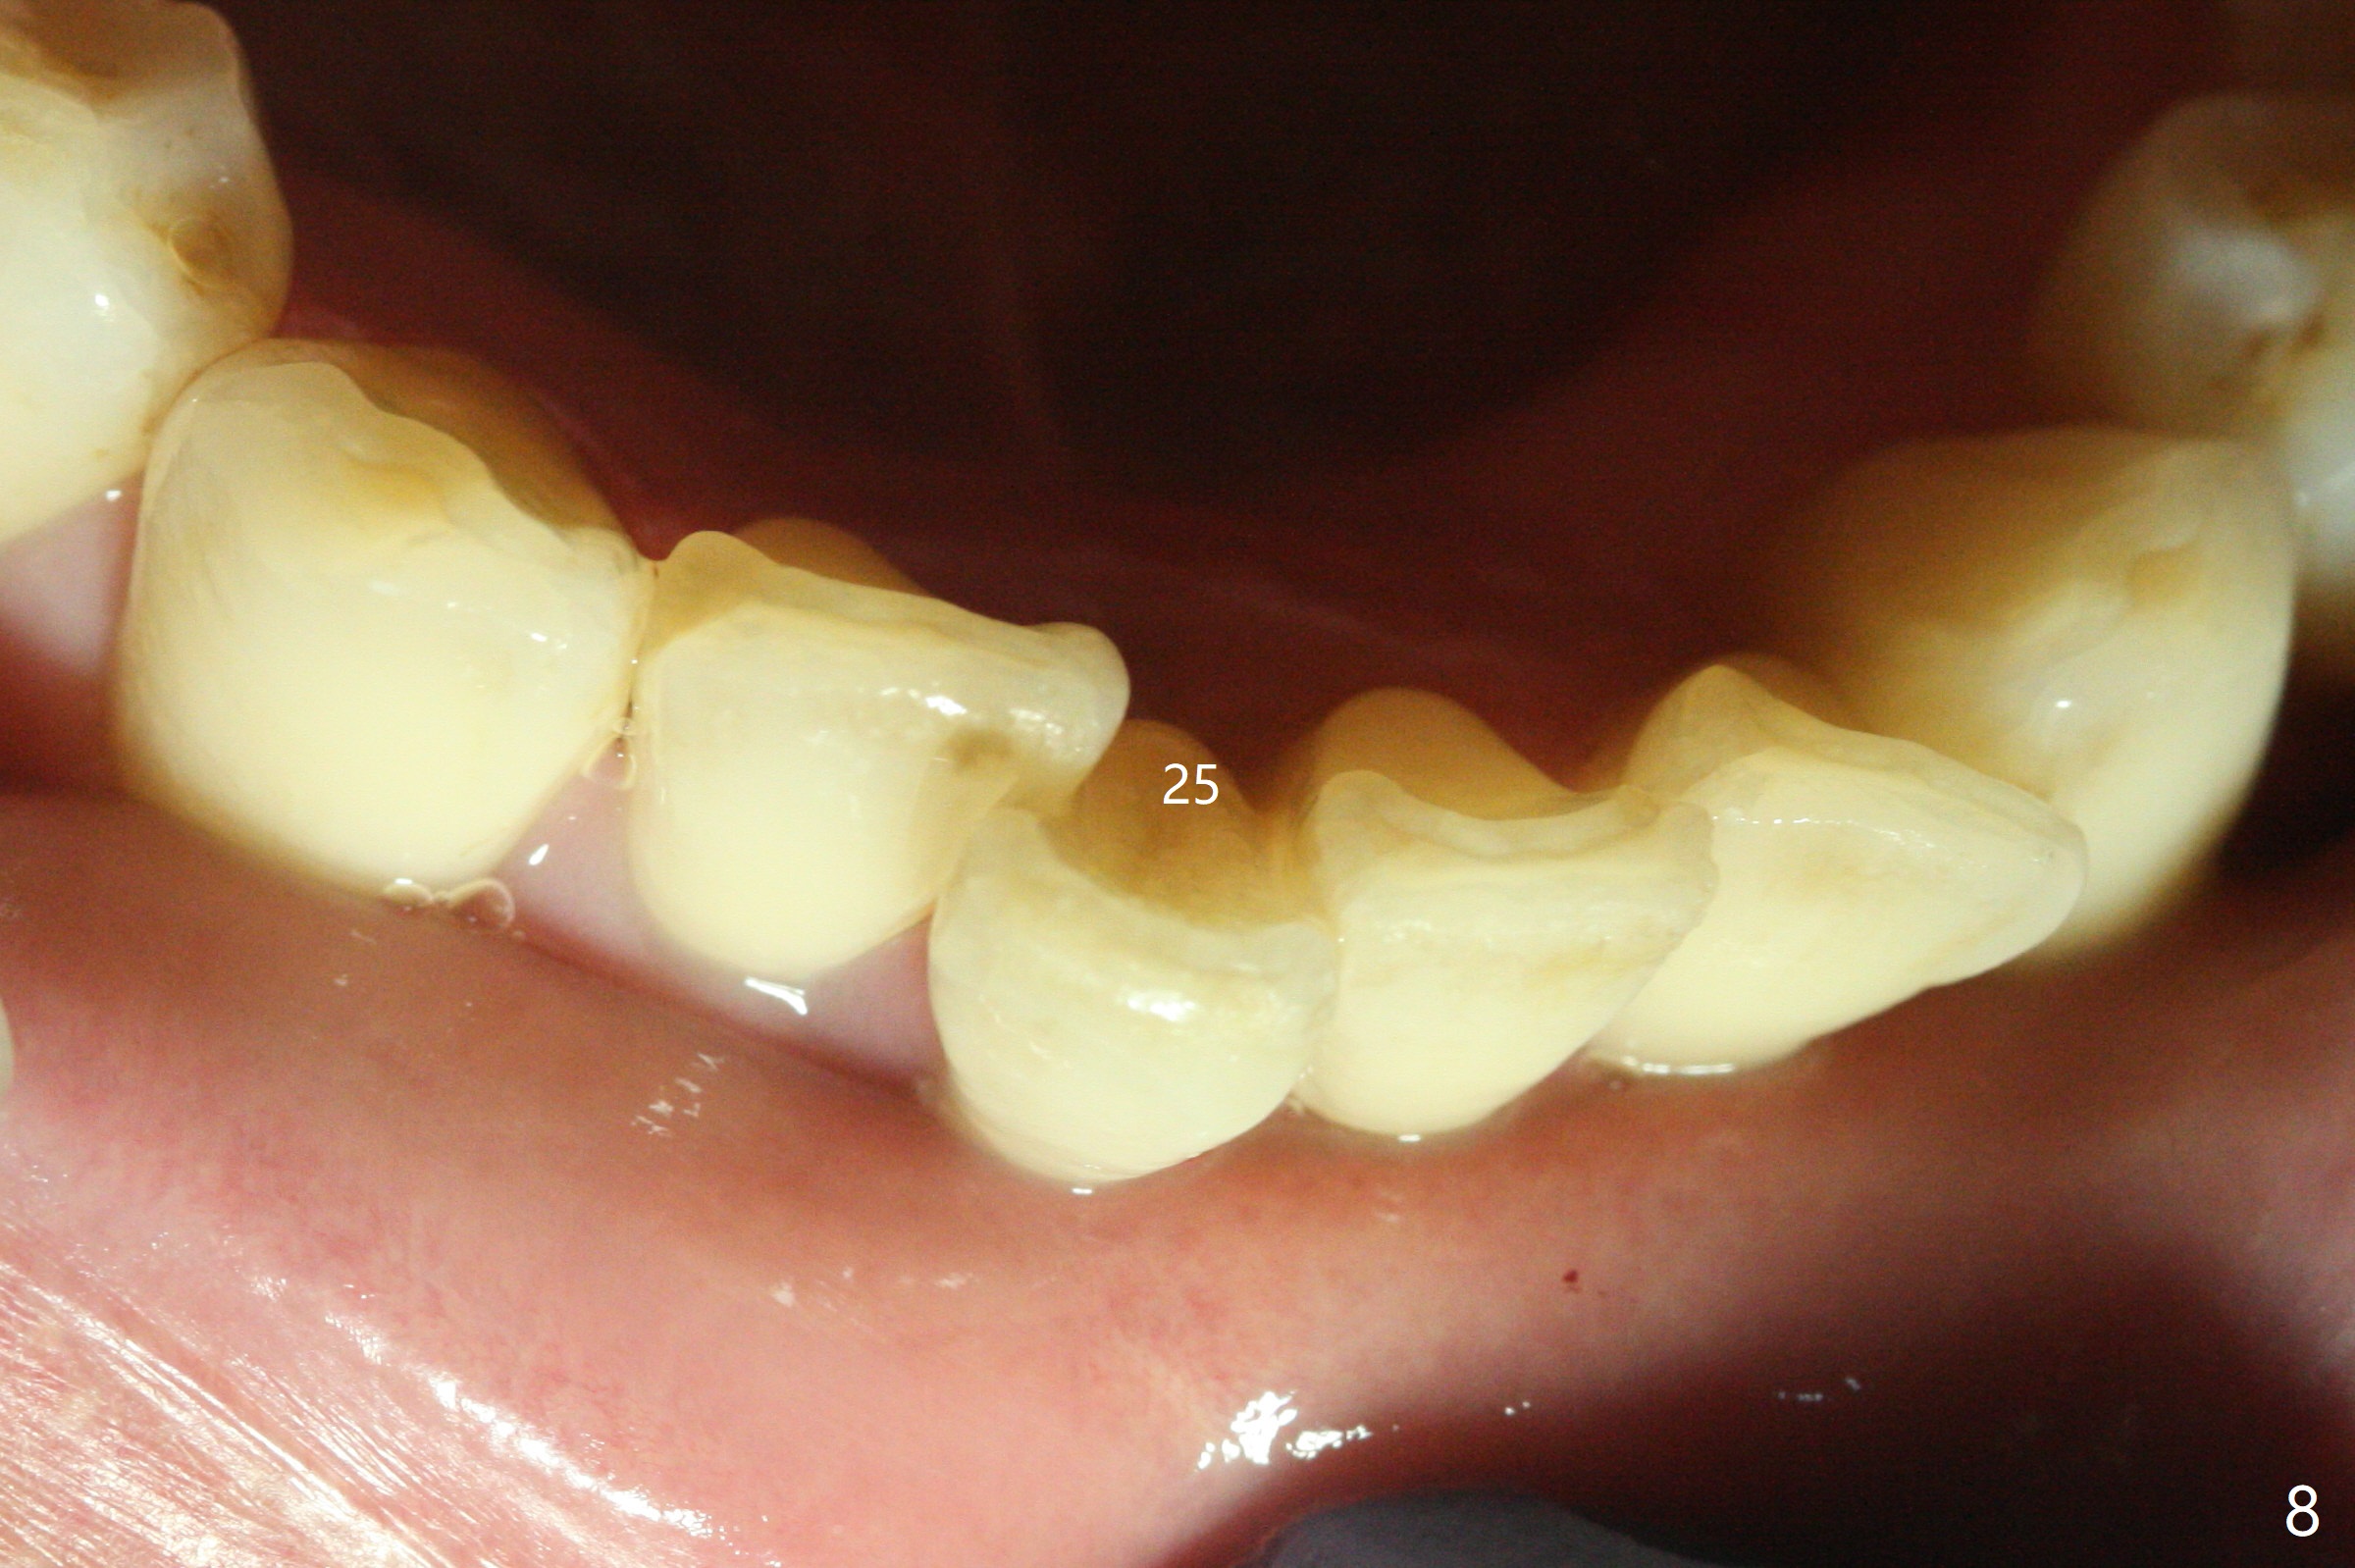

A 47-year-old man, a possible bruxer (Fig.1), is concerned about the mobile 2nd molar and lower central incisor (Fig.2,3). To prevent periimplantitis, a 2 mm 1-piece implant and a short one (5x5 mm) will be placed subcrestal at these sites, respectively (Fig.4,5). Sticky bone is a must. Pulpal test will determine whether RCT is required for #30 (Fig.5 curved white line). In fact the tooth #30 is tested to be vital. Onlay graft is an option for #31 (Fig.6 red rectangle). There is history of #32 extraction. The severely periodontally affected tooth #25 (Fig.7 *) has narrow mesiodistal space (Fig.8). It is the best treated with extraction with bone graft and self drifting.